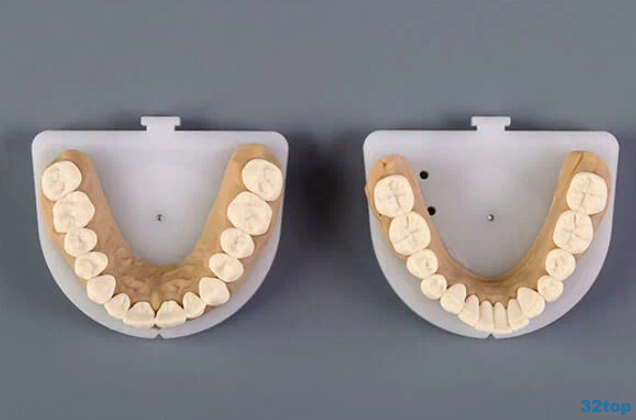

PRODENT CONCEPT (ПРОДЕНТ КОНЦЕПТ): работы специалистов (13)